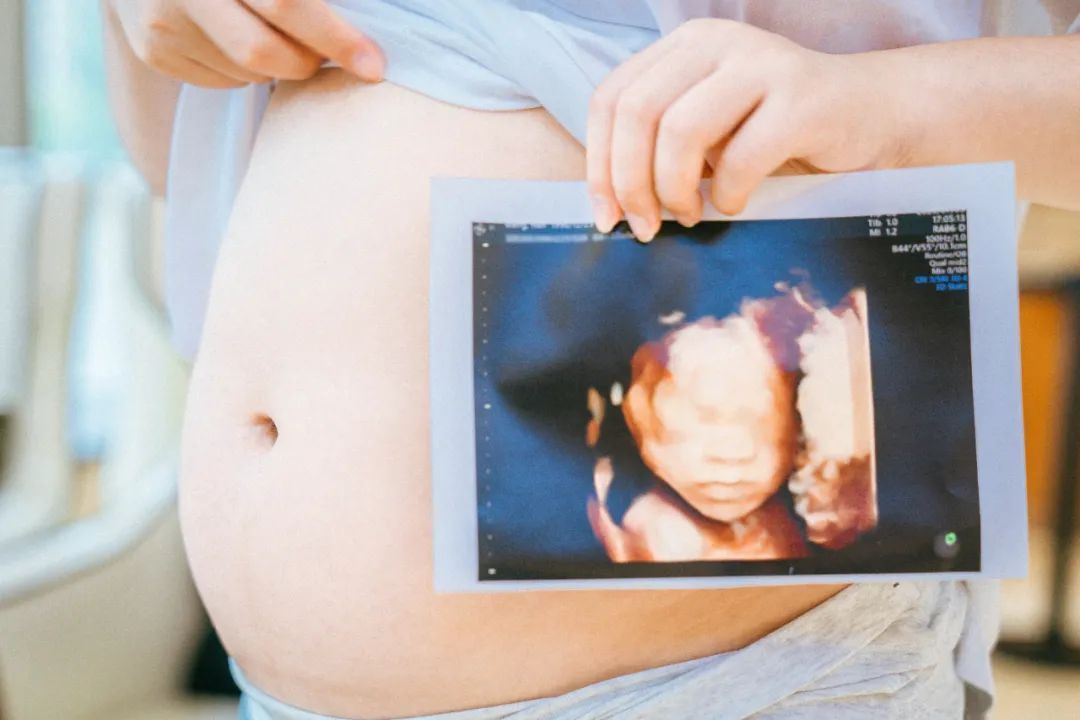

做过四维的妈咪都知道,要是刚好碰到宝宝趴着身子或是捂着小脸,妈妈们可就免不了狂吃甜食或来回运动、爬楼梯的一番折磨

。不过在和平的二楼导乐体验区域,助产士会根据准妈妈自身情况,运用专业医疗手法个性化调整胎位,帮助妈妈们一次看清宝宝正脸!